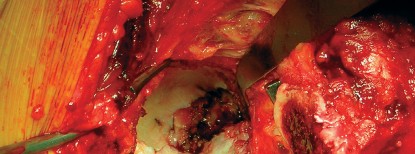

في جراحة استبدال مفصل الورك الكلي، يتم استبدال رأس عظم الفخذ التالف بمكون معدني كروي، ويتم استبدال الحُق الطبيعي المتضرر بمكون حُقي صناعي. المكون الحُقي الأسمنتي هو عبارة عن كوب معدني أو بلاستيكي عالي الجودة (عادة من البولي إيثيلين) يتم تثبيته داخل تجويف الحُق في عظم الحوض باستخدام "الأسمنت العظمي" (Bone Cement)، وهو مادة بوليمرية حيوية تعمل كغراء قوي لتثبيت المكون بشكل فوري ومستقر.

- جودة العظم (كثافة العظام): في حالات هشاشة العظام أو ضعف العظم، يوفر الأسمنت العظمي تثبيتًا فوريًا وموثوقًا به، مما يقلل من خطر الفشل المبكر.

- حالة العظم الحُقي: إذا كان هناك فقدان كبير للعظم أو تشوهات في تجويف الحُق، يمكن للأسمنت أن يملأ الفراغات ويوفر سطحًا مستقرًا للتثبيت.